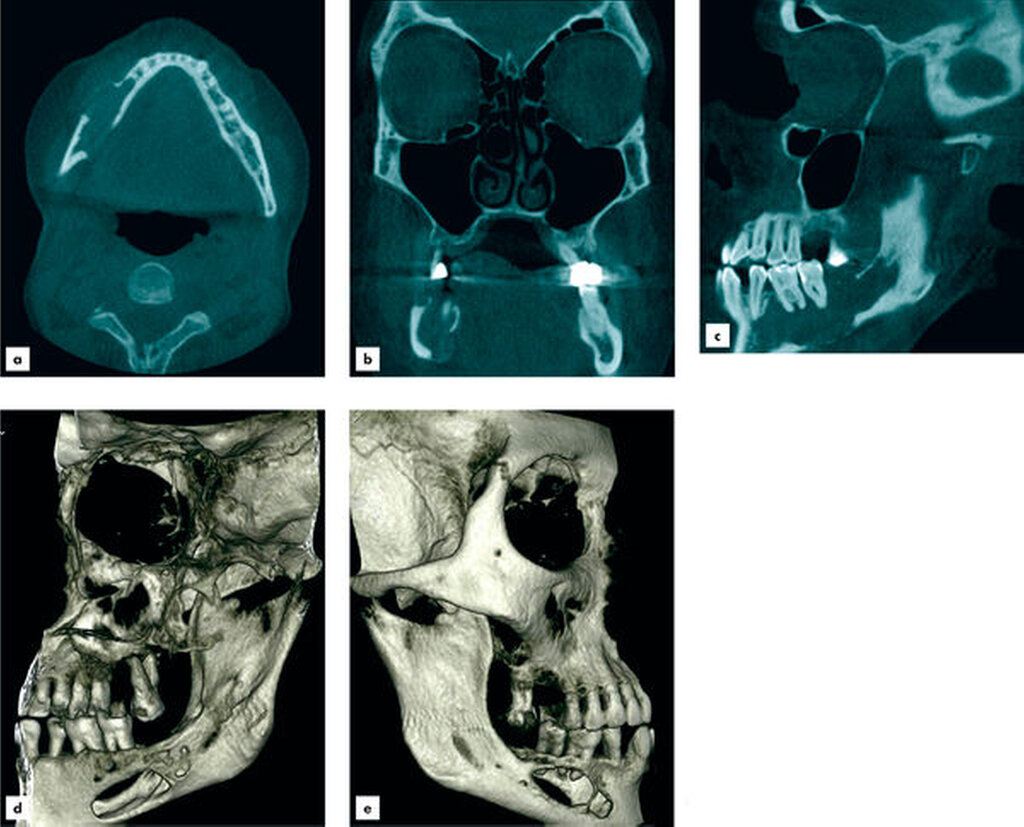

Aufgrund des klinisch unklaren Lokalbefunds in Zusammenschau mit dem radiologischen Befund wurde die Indikation zur Durchführung einer Digitalen Volumentomografie gestellt. Diese bestätigte eine von regio 45 bis in den aufsteigenden Unterkieferast reichende, etwa 6,5 cm lange zystische Läsion mit partieller Auflösung der Kortikalis. Die Wurzeln der sich in der Läsion befindlichen Zähne 47 und 46 wiesen keine Anzeichen einer Resorption auf. Innerhalb der Läsion waren knöcherne Septen zu erkennen, die auf einen multizystischen Prozess hinwiesen (Abbildung 2).